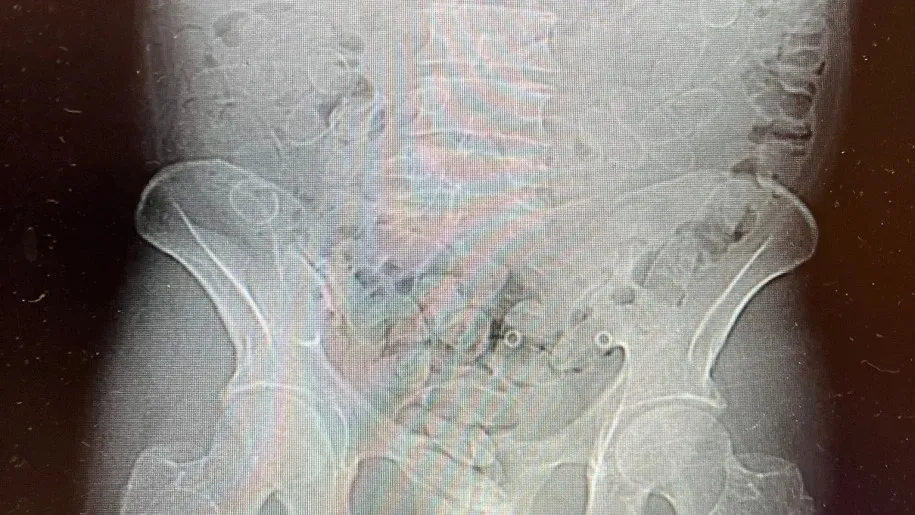

«Подальше обстеження за допомогою ультразвуку показало, що затриманий проковтнув ще 88 капсул із наркотиками, намагаючись приховати їх від контролю», — зазначають представники правоохоронних органів.

Загальна кількість вилученого наркотику разом із першою знайденою капсулою склала 89 одиниць.